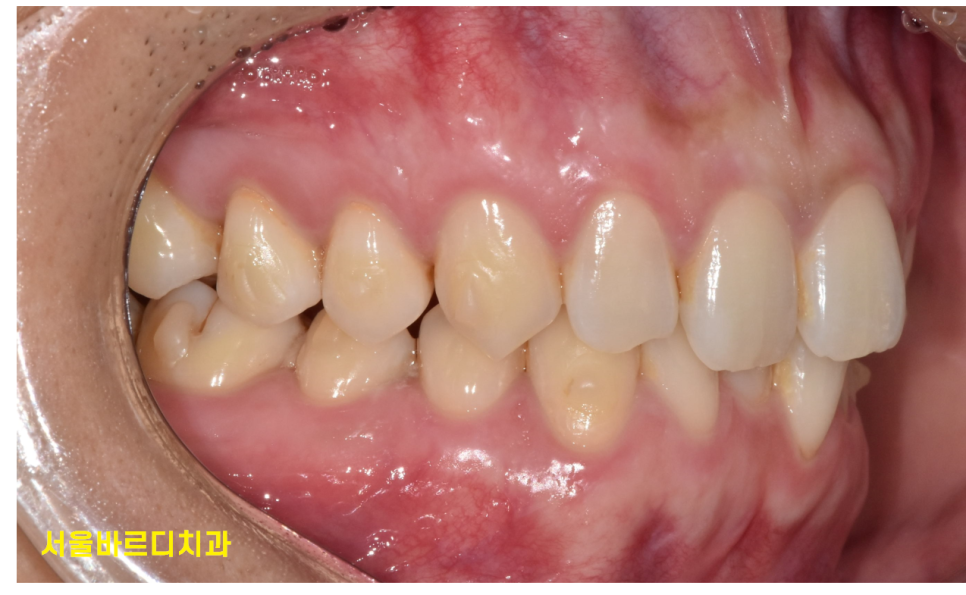

230725 투명교정하는 사람 입이라고는 전혀 모르시겠죠?

- 식사나 위생 관리가 용이한 장점

저는 세번째 장점이 가장 큰 것 같아요~

교정 중에는 치아와 교정 장치의 위생 관리가 중요합니다.

음식물이 부착되어있으면

쉽게 충치가 생길 수 있거든요~

잇몸이 붓기도 하고요.

투명교정 장치가 탈착이 가능하다보니

식사할 때는 빼고 밥을 먹게됩니다.

음식물이 교정장치에 끼는 문제를 방지할 수 있고

장치를 끼지 않은 상태에서 양치질을 할 수 있어

구강위생을 쉽게 관리할 수 있다 생각해요!

붙이는 교정장치에 비하여..

야외에서 하는 훈련중에는 양치가 쉽지 않을 수 있는데

이럴때 투명교정 장치는 정말 편리하거든요~